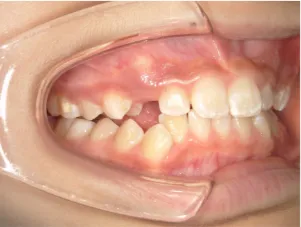

治療中③中1:非抜歯治療の診断で、上顎に歯の生えるスペースをつくるため上顎左右6をプレートで遠心移動し、隙間ができた時点

マルチブラケット法へ移行します

| 行ったご提案・診断内容 | 生え変わりが終わってなくマルチブラケット法による咬合治療には早い時期のため、顔立ちの成長を促す目的で歯列弓(アーチ)の拡大と前歯を並べながら永久歯が生えるのを待ち、咬合治療開始時に再診断で抜歯、非抜歯を最終検討する提案をしました。 再診断時(写真②)、歯列の拡大と上顎前歯の並べ替えはされていましたが八重歯となったため抜歯、非抜歯を検討しました。 口元は特に問題がなく非抜歯で八重歯を改善するためのスペースを作ることが可能なため非抜歯治療を提案しました。 治療は、 ・拡大および上顎左右6を遠心移動させてスペースを作る 予定装置 |